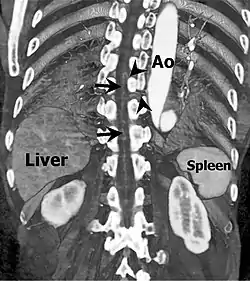

![]() Coronal slab volume rendering image of CT aortography shows artery of Adamkiewicz entering spinal canal(arrowheads) and joining the anterior spinal artery (arrows) after a hairpin turn. | |